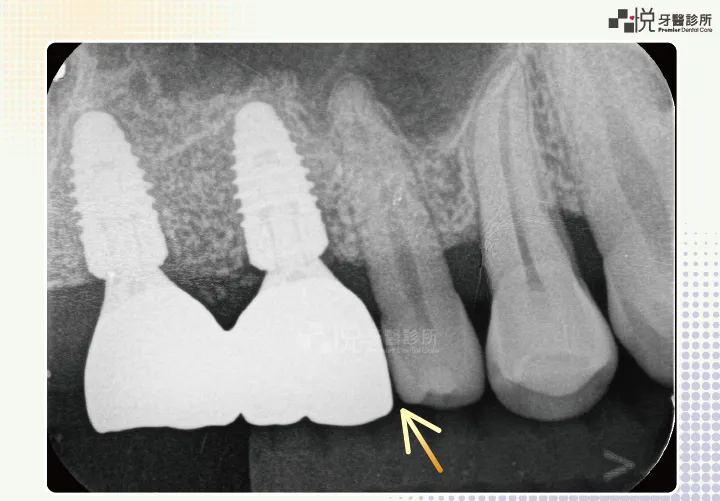

不論門牙、小臼齒、大臼齒,人工植牙就是只有一個圓柱形牙根。這是沒辦法跟真牙一樣的,因此牙齒跟牙齒間比較容易有「三角縫」,有時容易塞菜。醫師就算再怎麼盡力,也不一定能達到 100 分。

若植牙假牙下方地基凹陷,雖能植牙能正常使用,但還是較容易在地基凹陷處塞菜。

隨著我們成長、變老,真牙其實一直在移動,否則牙齒咬久了、磨損了,上下牙齒就咬不到、咬不好了。但植牙沒辦法像真牙一樣移動,因此久了可能會局部咬太重。有時也會發生真牙移動,但植牙不動,慢慢就出現一個牙縫。以上大多是臨床調整咬合跟修補假牙就能解決。